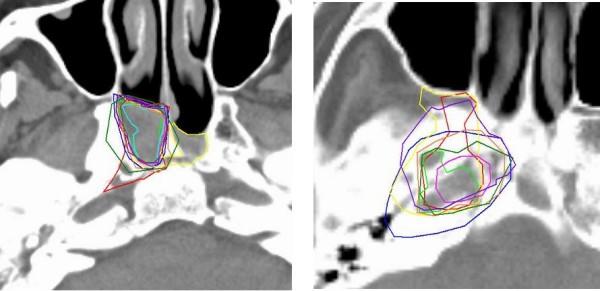

For ten nasopharyngeal cancer patients, ten observers each delineated the Clinical Target Volume (CTV) and the CTV elective. After 3D analysis of the delineated volumes, a second delineation was performed. This implied improved delineation instructions, a combined delineation on CT and co-registered MRI, forced use of sagittal reconstructions, and an on-line anatomical atlas.

Both for the CTV and the CTV elective delineations, the 3D SD decreased from Phase 1 to Phase 2, from 4.4 to 3.3 mm for the CTV and from 5.9 to 4.9 mm for the elective. There was an increase agreement, where the observers intended to delineate the same structure, from 36 to 64 surface % (p = 0.003) for the CTV and from 17 to 59% (p = 0.004) for the elective. The largest variations were at the caudal border of the delineations but these were smaller when an observer utilized the sagittal window. Hence, the use of sagittal side windows was enforced in the second phase and resulted in a decreased standard deviation for this area from 7.7 to 3.3 mm (p = 0.001) for the CTV and 7.9 to 5.6 mm (p = 0.03) for the CTV elective.

材料与方法

结果

无论是 CTV 还是 CTV 选择性勾画,3D 标准差都从第 1 阶段到第 2 阶段降低,CTV 从 4.4 降至 3.3mm,CTV 选择性从 5.9 降至 4.9mm。观察者对同一结构的勾画意向一致性增加,CTV 从 36%增加到 64%(p=0.003),CTV 选择性从 17%增加到 59%(p=0.004)。勾画的最下部边界变化最大,但当观察者使用矢状位窗时,这些变化较小。因此,在第 2 阶段强制使用矢状位侧窗,使 CTV 和 CTV 选择性的该区域标准差从 7.7 降至 3.3mm(p=0.001)和 7.9 降至 5.6mm(p=0.03)。